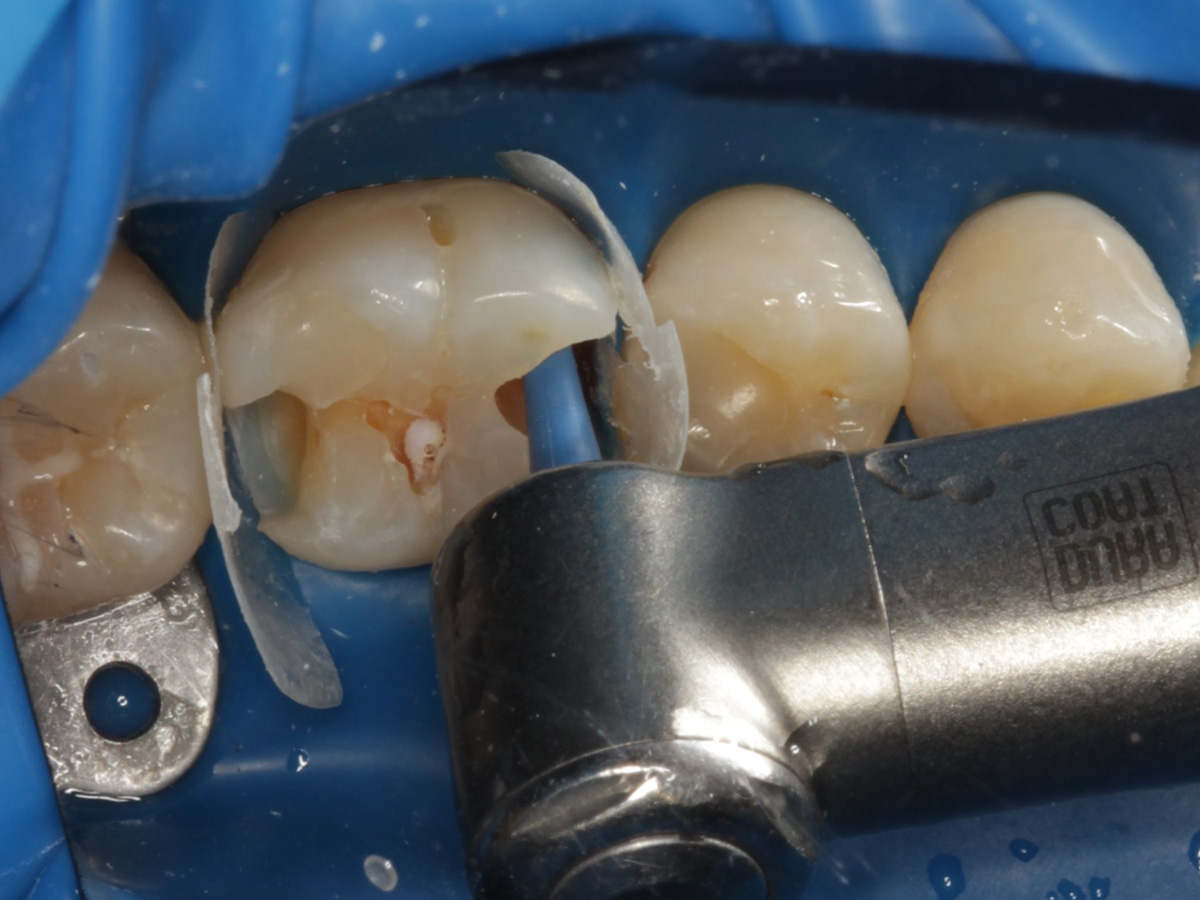

Abbildung 1

Intakte Kaufläche bei Approximalraumkaries an Zahn 36 mesial und distal

Quadrantenisolierung mit Kofferdam (x-heavy)